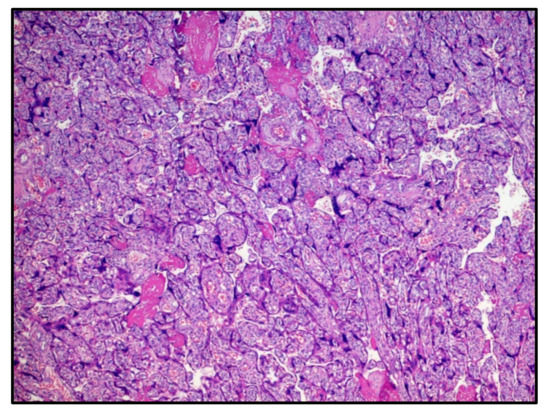

The first chorionic disc corresponded to the gestational age and presented very large areas of intervillous fibrinous deposition (Figure 1) with the presence of numerous perivillary histiocytes. Minor recent infarct foci were also described, while umbilical cord and amnio–chorionic membranes were completely normal. The immunohistochemical reaction for the SARS-CoV-2 protein S1 was strongly expressed both in the syncytiotrophoblast cells and in the perivillary histiocytes described in H&E (Figure 2).

Figure 2. Immunostaining for anti-SARS-CoV-2 spike protein S1 positive at the level of the syncytiotrophoblast and perivillary histiocytes. (IHC, Original Magnification: 10×).